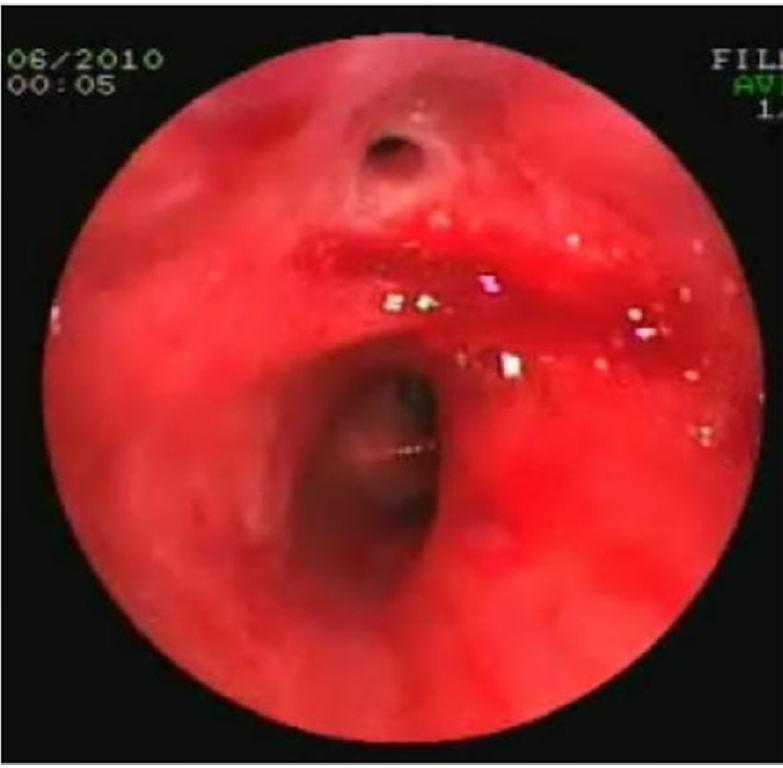

・耳鼻科へ緊急コンサルトされ、喉頭ファイバー検査を実施

◦声門下領域に管腔外病変が疑われた